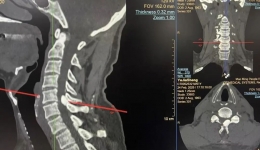

近日,茂名市人民医院脊柱外科二区团队为一名在凌晨突发剧痛、上肢麻痹的急性自发性椎管内硬膜外血肿(ASSEH)高龄患者实施了高风险的急诊手术,最终化险为夷,帮助患者重新站立行走。罕见急症突袭,七旬老人命悬一线近日,70多岁的许大爷(化名)...